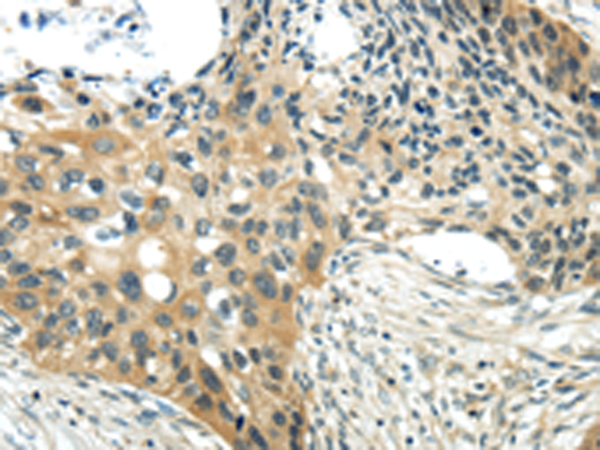

分类: 科研抗体货号: P12420别名: WNT13应用: IHC反应种属: Human, Mouse